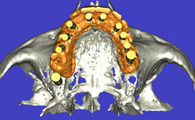

IMPLANTOLOGIE : LA CHIRUGIE GUIDEE